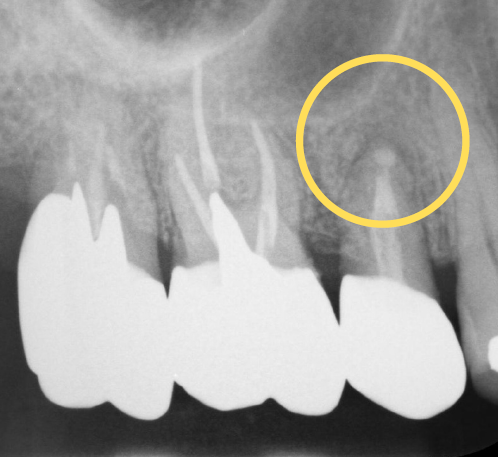

治用前の状態がこちらです

レントゲンを見ると、以前根っこの治療をしたところに膿がたまっているのがわかります。また、奥歯の被せ物も古くなり段差ができてあわなくなってきています。